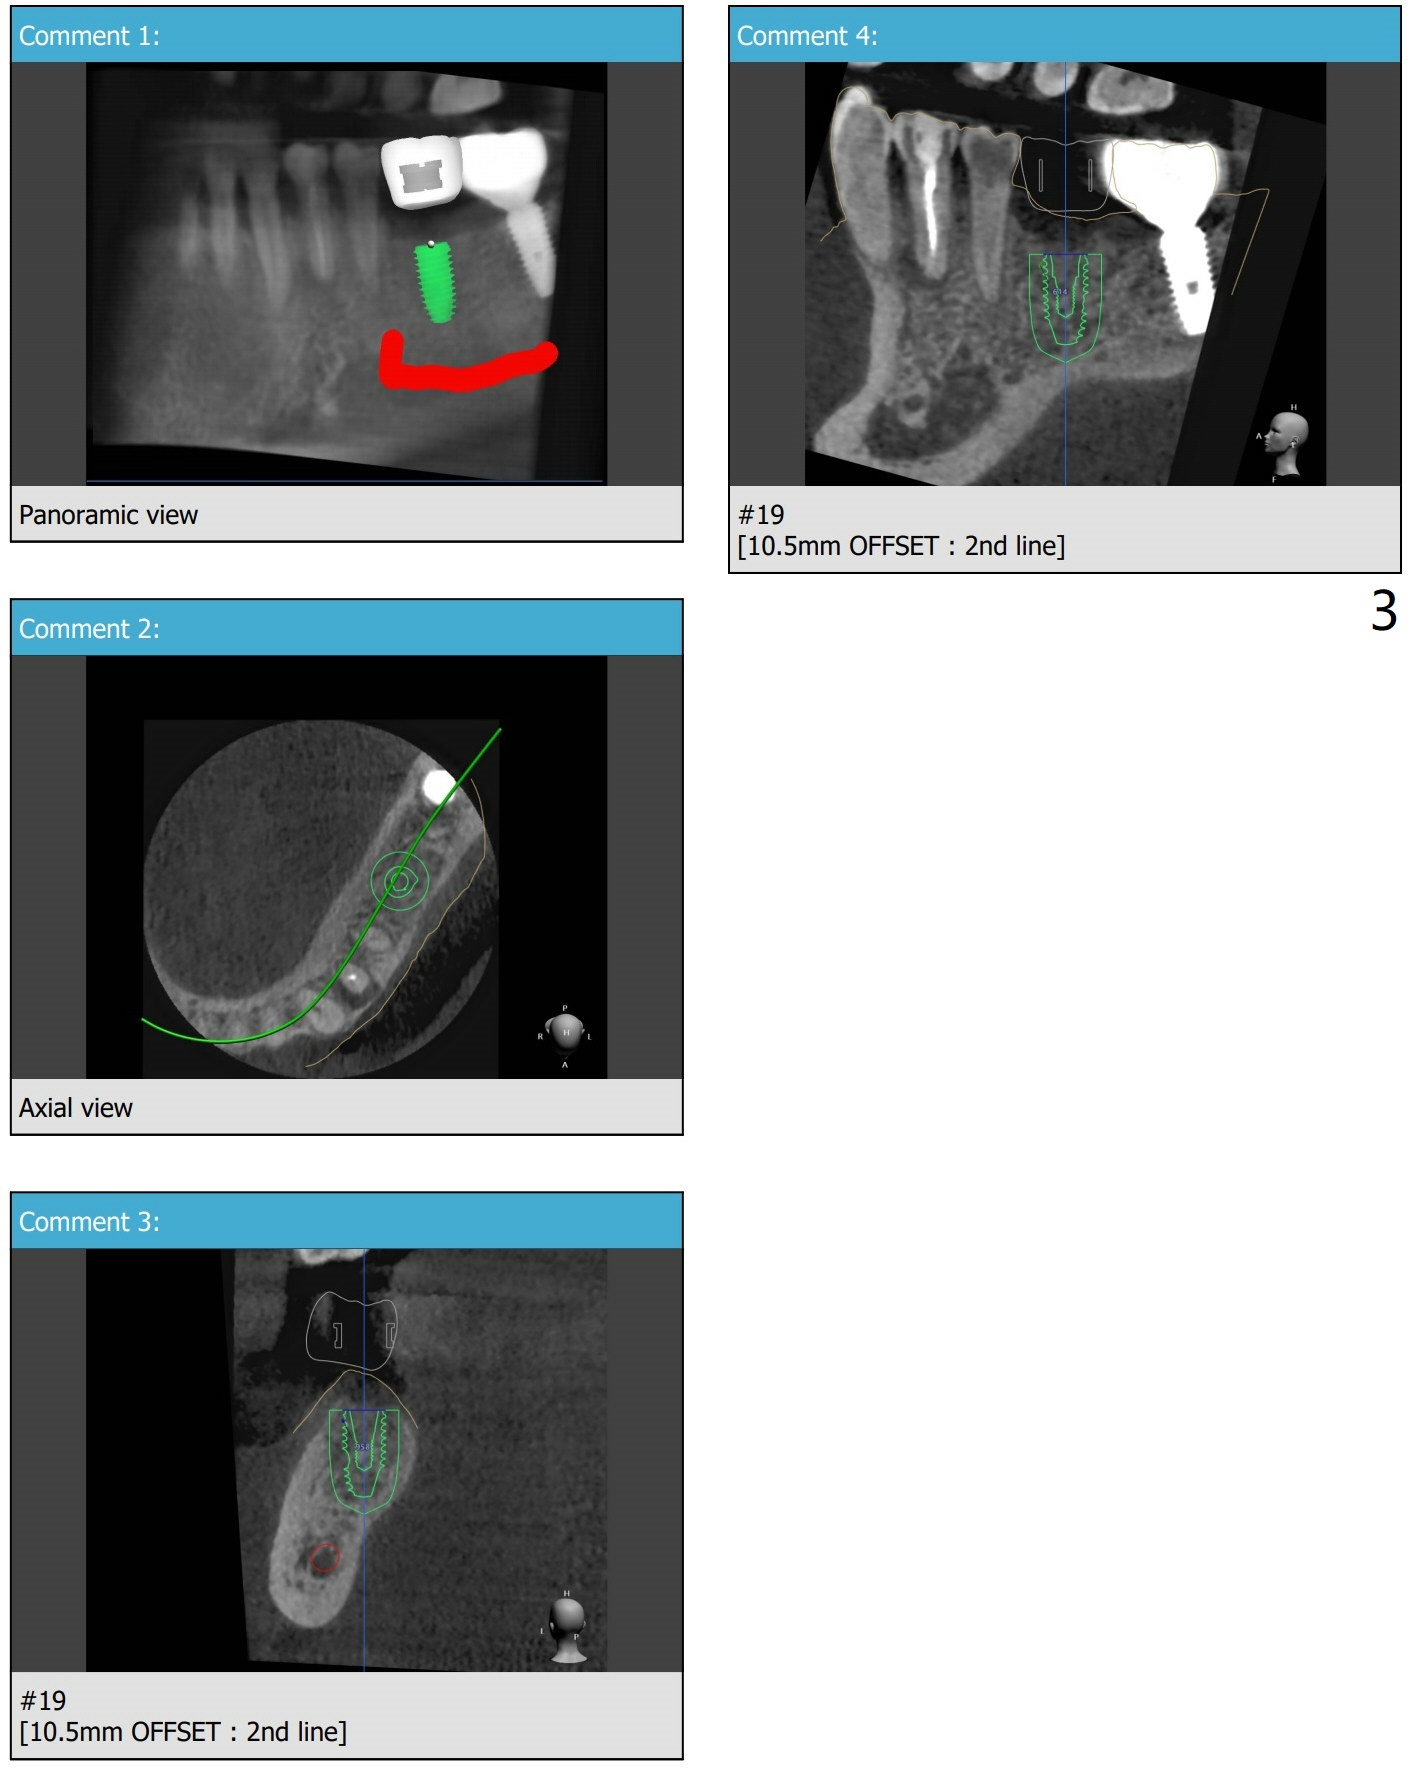

下颌第一磨牙植体长度取决因素

Submandibular Fossa, UF

Return to No Deviation